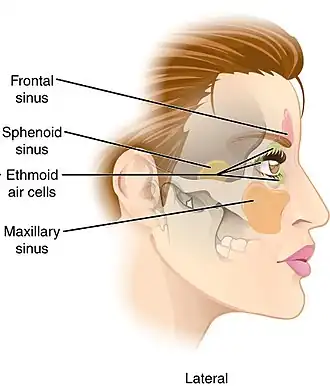

Lateral projection of the paranasal sinuses | |

Paranasal sinuses are a group of four paired air-filled spaces that surround the nasal cavity.[1] The maxillary sinuses are located under the eyes; the frontal sinuses are above the eyes; the ethmoidal sinuses are between the eyes, and the sphenoidal sinuses are behind the eyes. The sinuses are named for the facial bones and sphenoid bone in which they are located. The role of the sinuses is still debated.

Humans possess four pairs of paranasal sinuses, divided into subgroups that are named according to the bones within which the sinuses lie. They are all innervated by branches of the trigeminal nerve (CN V).

- The maxillary sinuses, the largest of the paranasal sinuses, are under the eyes, in the maxillary bones (open in the back of the semilunar hiatus of the nose). They are innervated by the maxillary nerve (CN V2).[2]

- The frontal sinuses, superior to the eyes, in the frontal bone, which forms the hard part of the forehead. They are innervated by the ophthalmic nerve (CN V1).[2]

- The ethmoidal sinuses, which are formed from several discrete air cells within the ethmoid bone between the nose and the eyes. They are innervated by the ethmoidal nerves, which branch from the nasociliary nerve of the ophthalmic nerve (CN V1).

- The sphenoidal sinuses, in the sphenoid bone. They are innervated by the ophthalmic and maxillary nerve (CN V1 and V2).[2]